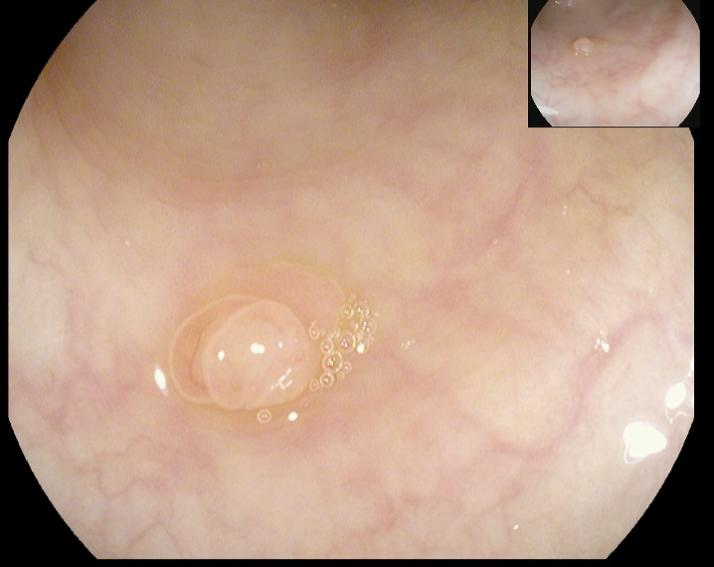

(1)赖女士(62岁,横结肠息肉,图1)

肠镜一照,息肉现形!形态各异的大肠息肉,离癌有多远?(图1)

图1

病理诊断:管状腺瘤,伴低级别上皮内瘤变。

解读:管状腺瘤是最常见的腺瘤性息肉。低级别上皮内瘤变意味着腺体结构和细胞出现了轻度到中度的异常改变,是明确的癌前状态。此阶段积极切除并定期复查,可有效阻断癌变进程。距离癌:一步之遥,癌前病变中期。